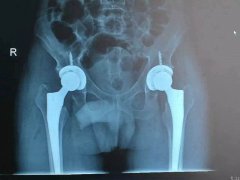

近日,我院骨科成功為一名老年男性患者實施雙側股骨頭無菌性壞死人工髖關節(jié)小切口DA……